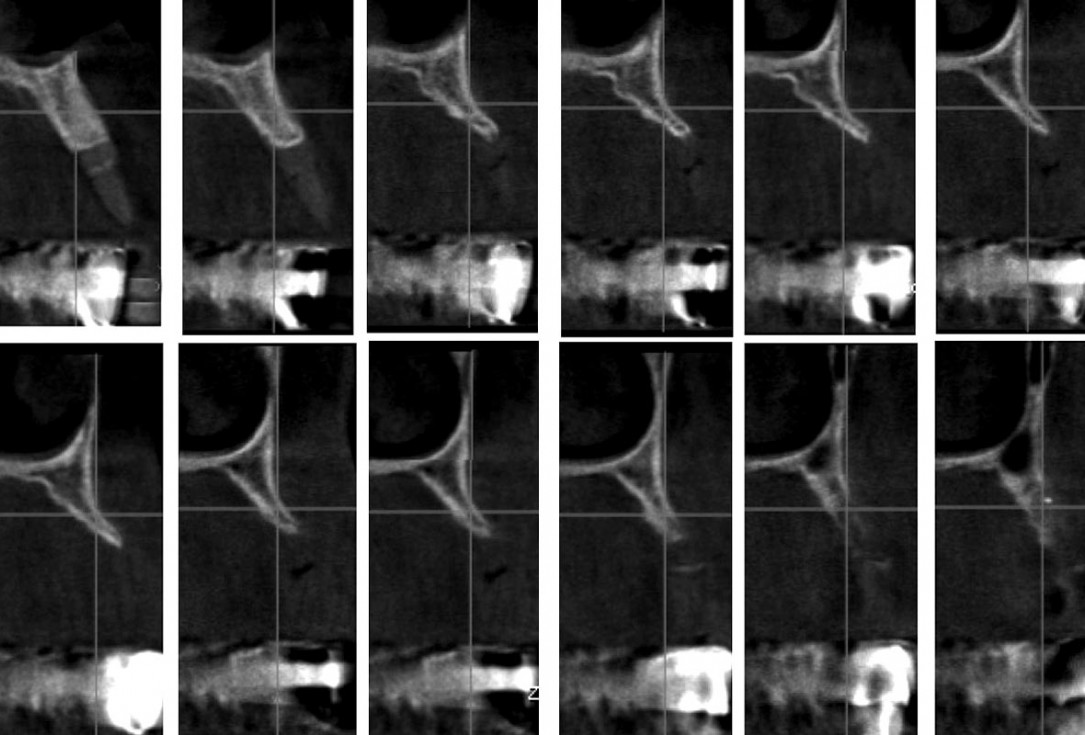

10/16 - CBCT after 6 months – successful integration, no gaps between block and residual bone

Reconstruction of Anterior Maxilla with maxgraft® bonebuilder – Dr. B. Han